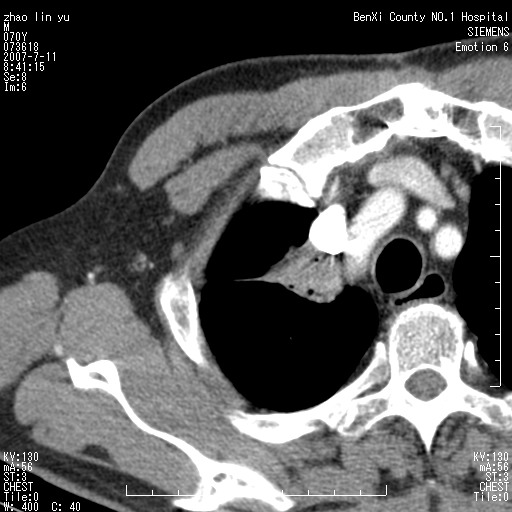

以下是引用王靖旗在2007-7-10 17:12:00的发言:[br] 男、70、咳嗽两个月,半年前换瓣手术,胸片未见异常,于昨天行x片发现右肺上野大片影,行ct扫描,这里是减薄图像,余肺正常。明天晚上会有增强扫描片,到时我会上传。[br][br] 冠状位请大家细看,应该是有意义的,[br][br] 请大家先看平扫发表意见。[br][br]

以下是引用zhangzhongshou在2007-7-10 21:43:00的发言:[br]右肺上叶周围型肺癌,以孤立型细支气管肺泡癌可能性大。